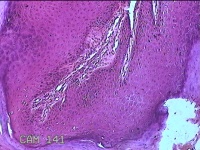

头部肿物

性别

男

年龄

21岁

临床诊断

头皮肿物

一般病史

发现头部结节10余年,无明显疼痛及不适。

标本名称

头部结节

大体所见

灰白暗红色带皮肤样结节1.5x1.3x0.3cm一个,切开结节呈实性,切面灰白粉红色,质软。